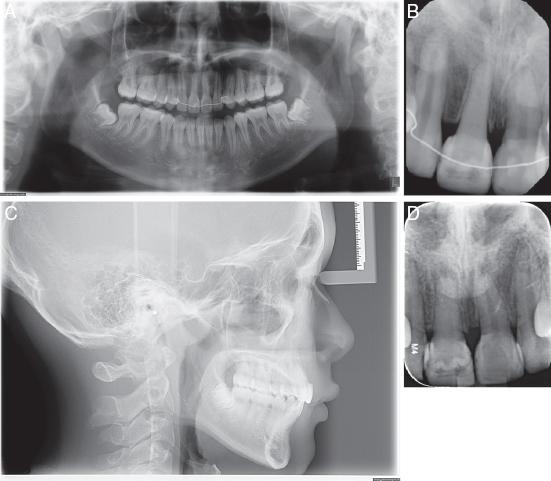

An 11-year-old healthy girl visited the clinic with the chief complaints of an uneven smile, after suffering dental trauma to her upper incisors (Figure 7A-H). The upper right lateral incisor (#12) and upper left central incisor (#21) had been subluxated, while the upper right central incisor (#11) suffered a complicated crown fracture which extended subgingivally. Teeth #12 and #21 were root canal treated and displayed radiographic evidence of progressive replacement resorption, while #11 was decoronated 2 mm below the cemento-enamel junction for alveolar bone preservation (Figure 8A-D). She was referred by the paediatric dentist for multidisciplinary management and extractions of #12 and #21, after infra-occlusion of these teeth was observed.

(A) Pretreatment panoramic radiograph. (B) Periapical radiograph showing decoronated #11 and crown attached; Resorption on the apical surfaces of #12 and #21. (C) Lateral cephalogram. (D) CBCT section showing developing tooth #35 with ⅔ root length and (E) Developing tooth #45 with ¾ root length.